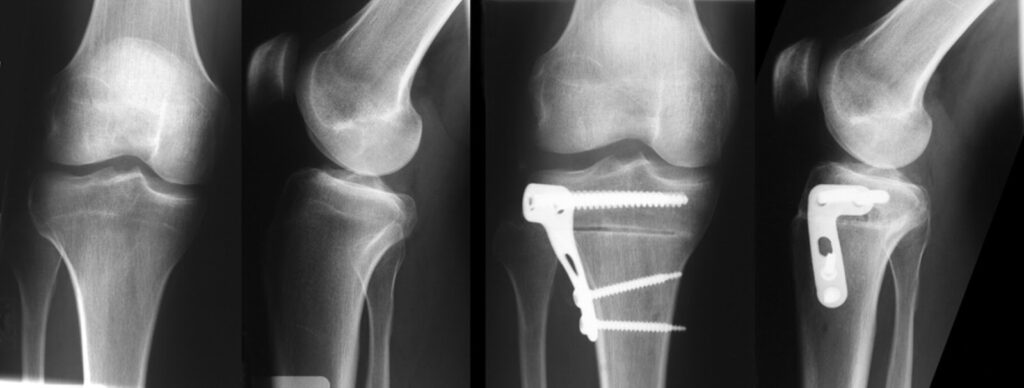

The global osteotomy plates industry refers to the industry involved in the production, distribution, and sales of plates used in osteotomy procedures. Osteotomy is a surgical procedure that involves cutting and reshaping bones to correct deformities, realign joints, or treat conditions such as arthritis. Osteotomy plates are implantable medical devices used to stabilize and support the bones during the healing process after an osteotomy.

These plates are typically made of biocompatible materials such as stainless steel or titanium. They are designed with screw holes and other features to allow for precise fixation and alignment of bone segments. Osteotomy plates come in various shapes, sizes, and configurations to accommodate different surgical needs and anatomical considerations.